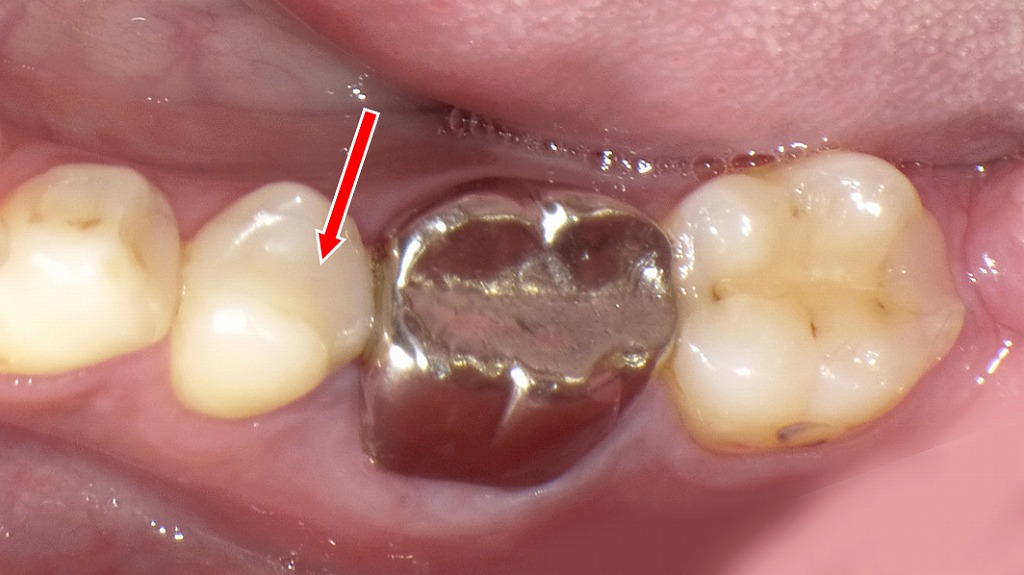

この画像は左下第2小臼歯(5番)を示しています。赤い矢印で示された歯には、CAD/CAMインレー(ハイブリッドセラミックインレー)が装着されています。

🦷 観察ポイント

- 詰め物の素材

銀歯ではなく、歯とほぼ同じ色調の白いインレーが確認できます。

これはレジンとセラミックを混合したハイブリッドセラミック製で、CAD/CAMシステムにより設計・削り出されたものです。 - 隣接面の適合性

隣の銀歯(左下第1大臼歯)との接触点も適切で、段差や隙間が見られません。

デジタル設計による高い精度で作製されていることが分かります。 - 形態・色調

咬合面の形態が自然で、歯の丸みやツヤも周囲の天然歯とよく調和しています。

わずかに明るめの色ですが、審美的に非常に自然な印象です。

💬 臨床的評価

左下5番のCAD/CAMインレーは良好に適合しており、辺縁漏洩や咬合不調の兆候は認められません。

清掃状態も良好で、プラーク付着や着色もほとんどありません。

保険適用の白い詰め物として機能的・審美的に安定しており、長期経過も期待できます。